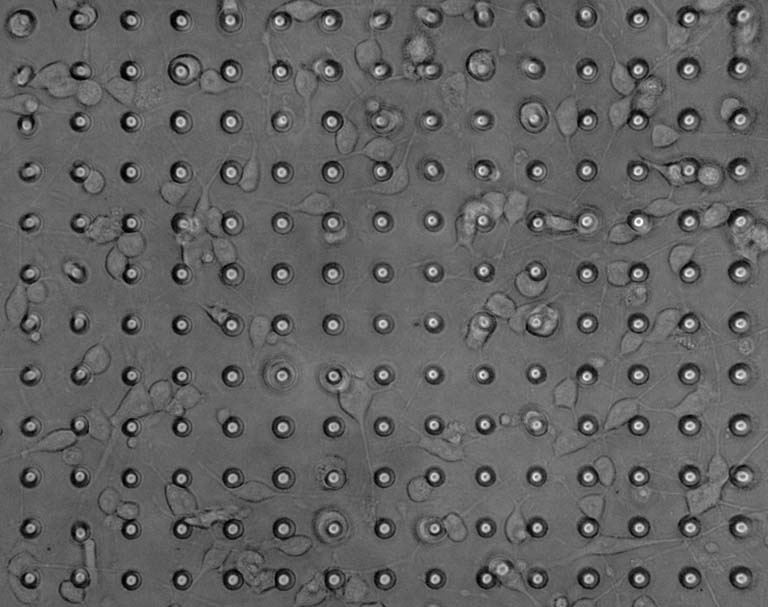

This image collection depicts the use of biocompatible 3D-printed materials to study the process of myelination, or wrapping of membranes around neuronal axons in the central nervous system, by oligodendrocyte cells. The process of myelination is involved in a myriad of disorders for which no therapies have been successfully developed. Understanding causes and potential treatments of disorders characterized by incomplete myelin production or myelin degeneration are particularly challenging due to a lack of predictive preclinical tools. Using these Artificial Axons, we can stimulate and quantify oligodendrocyte myelination in a well-defined environment that recapitulates key physical, mechanical and chemical properties of central nervous cells and tissues.